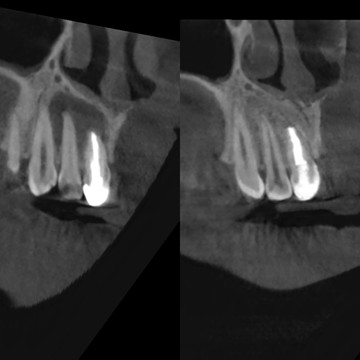

На снимке врач видит примерно такую картинку: чёрное облачко вокруг корня — это и есть периодонтит

Хронический апикальный периодонтит редко кто приходит лечить специально. Чаще всего его обнаруживают случайно: стоматолог делает рентген, а там — чёрное облачко вокруг корня зуба. Вот так он и выглядит.

Когда инфекция попадает в организм — в любом месте, будь то ссадина на коленке или депульпированный зуб, по всем каналам разносится сигнал: «SOS! Опасность! Микробы наступают!» И специальные клетки крови, в том числе нейтрофилы, «сбегаются» отовсюду, чтобы уничтожить заразу, которая пытается попасть в кровеносное русло и костную ткань. Если инфекцию не убрать и ранку не промыть, то появится гнойник — скопление погибших в неравной борьбе нейтрофилов, отмерших клеток, погибших микробов. Чем больше инфекции, тем больше специальных клеток иммунитета приходит в очаг для борьбы с инфекцией и растворяет не только микробы, но, к сожалению, и костную ткань. Разрушенный очаг этой костной ткани мы и видим на рентгене. То есть это не микроб приходит пожирать кость, её уничтожают наши собственные клетки, пусть и невольно. Если где-то возникает очаг, это значит, что идёт серьёзная борьба, в которой мы пока проигрываем.